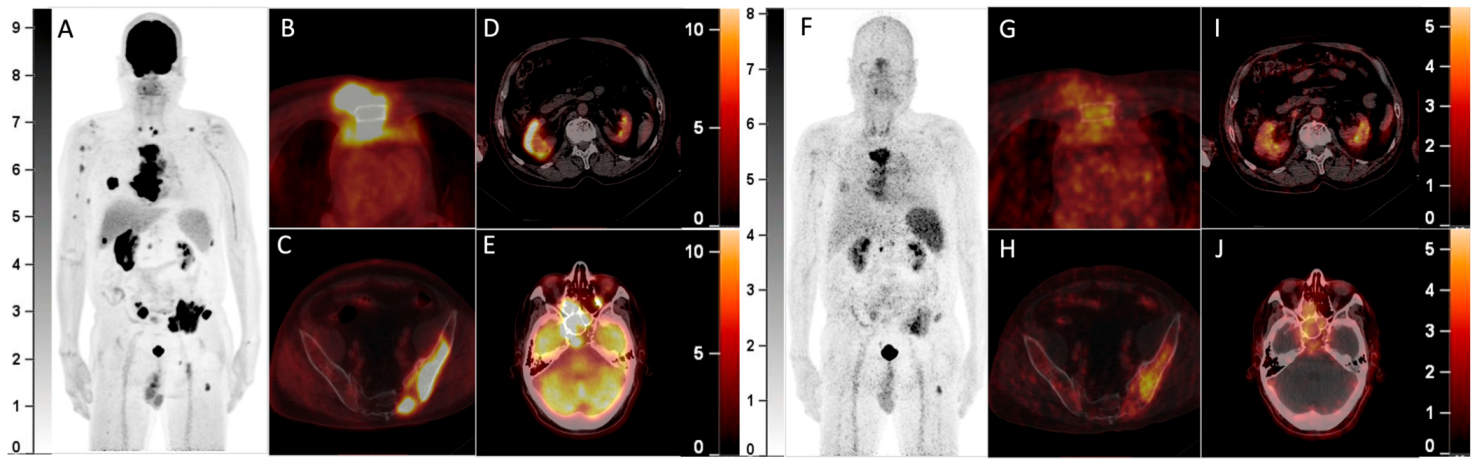

A 64-year-old man with a history of multiple myeloma (MM) for 8 years, recently presented with a parasternal mass and blindness of the right eye. Serum protein electrophoresis and immunofixation electrophoresis showed positivity for the monoclonal protein (16.2 g/L, IgA-λ). A biopsy of the parasternal mass confirmed plasmacytoma. Considering the recurrence of MM, 18F-FDG PET/CT was referred. The maximum intensity projection (MIP) of the PET (A) detected multi-foci with intense radioactivity all over the body. The axial fusion images (B,C, bone window) showed most of the FDG-avid foci were located in bone marrow, most prominently in the sternum and pelvis (SUVmax 34.0), accompanied by lytic bone destruction and paramedullary masses. Additionally, the axial fusion images (D,E, soft tissue window) demonstrated extramedullary disease (EMD) with intense FDG uptake in the right kidney and paranasal sinus (SUVmax 22.3), which also involved the right orbit and temporal lobe. Since 68Ga-Pentixafor has been reported to be advantageous over 18F-FDG in assessing MM1,2, he was included in the clinical trial of 68Ga-Pentixafor (NCT03436342). In the MIP (F) and corresponding axial fusion images of 68Ga-Pentixafor PET (G–J), the above hypermetabolic foci showed significantly lower tracer uptake as compared with 18F-FDG PET (bone marrow lesions: SUVmax 16.5; EMD: SUVmax 7.4).